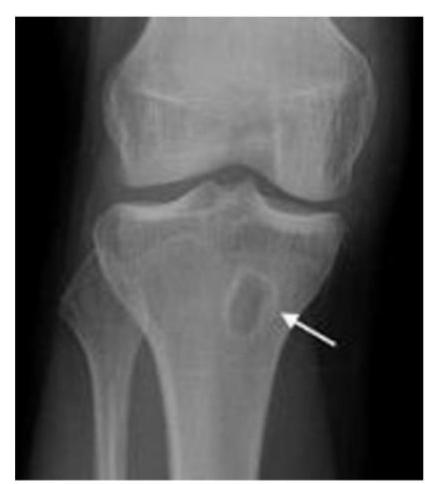

A teenager with acute onset of pain in the right hip during a run. He sustained the injury seen in the x-rays with a white arrow. This injury usually occurs due to a forceful eccentric contraction of which of the following muscles?

- C. Rectus femoris

Which of the following muscles is attached to the structure pointed by the arrow?

- C. Sartorius

Note: Arrow was pointing at ASIS (Anterior Superior Iliac Spine)